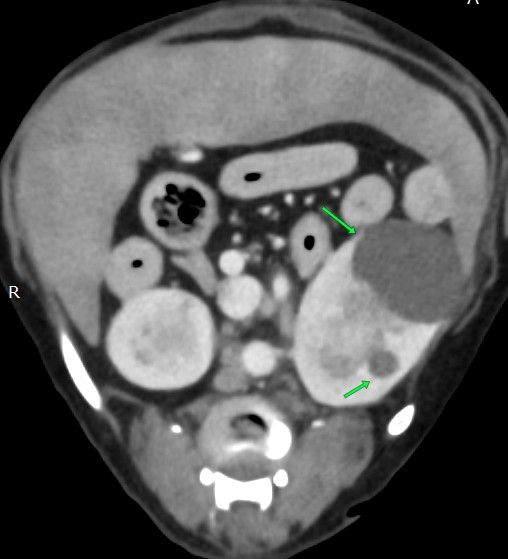

腫瘍を疑い手術ですので、術前にCT検査です

①脾臓の腫大

②左右に大きな腎臓に嚢胞

③胆石あり

色々見つかりました

①は転移の可能性もあるので手術時に脾臓の細胞検査

②腎不全になりやすいので点滴をしっかり

③今後の要注意

やはり高齢は一筋縄ではいきません